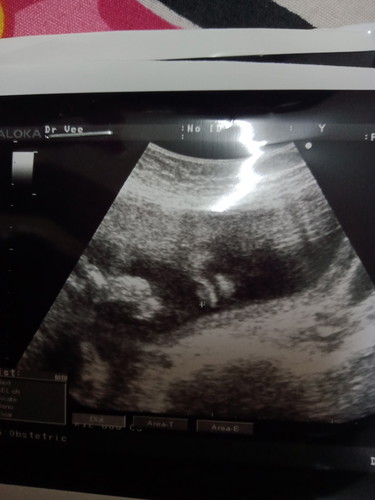

ตั้งครรภ์29+4วัน เราคิดไปเองรึเปล่าคะ ว่าคือตาจมูกลูกเรามันจะชัดขนาดนั้นเลยออคะ ที่ขฃคุนหมอทำเครื่องหมายคือส่วนปากคะ แต่เรามองๆดูเหมือนเห็นจมูกตาด้วย

ปกติอายุครรภ์ขนาดนี้น้องมี ตา จมูกแล้ว แต่รูปนี้ไม่ชัดนะคะ นี่ตอน25วีคค่ะ เห็นอ้าปากชัดๆเลย